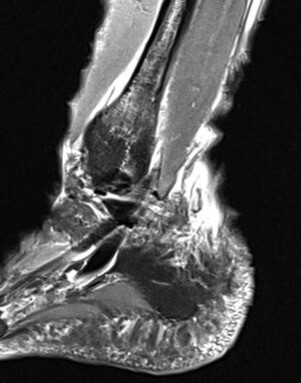

Anamnese: Die Patientin stellte sich zunächst mit Schmerzen im Bereich des linken OSG vor, nachdem sie auf Grund sehr eisiger Verhältnisse im Januar mit Grödel über 10 km gelaufen sei. Zudem habe sie eine Schwellung im Bereich der distalen Fibula bemerkt. Medikamente wurden nicht eingenommen, Vorerkrankungen waren keine bekannt. Bei der körperlichen Untersuchung bestand deutliche Druckdolenz und klar lokalisierbarer Klopfschmerz im Bereich der distalen Fibula dia-metaphysär linksseitig sowie eine Schwellung des OSG mit im Seitenvergleich ca. 2 cm Umfangsvermehrung an der Fibulaspitze. Das OSG sowie USG zeigte sich stabil, ein Talusvorschub bestand nicht. Die Rückfußposition war regelrecht, die Rückfußsehnen ohne Funktionseinschränkung. Eine deutliche Einschränkung bestand in der Dorsalextension sowie in der Eversion. Sonografisch zeigte sich eine subperiostale Schwellung als mögliches Zeichen eines Hämatoms mit fraglicher Unterbrechung des Periosts. Zur weiteren Abklärung erfolgte eine MRT des linken OSG. Dieses ergab eine frische Stressfraktur der distalen Fibula im Bereich der distalen Diaphyse und Metaphyse ohne Nachweis einer Dislokation mit periossärer Weichteilödematisierung (Grad IV nach Arendt und Griffiths) (vgl. Abb. 1Abb. 2).

Vor der Behandlung zeigte der AOFAS Score 40 Punkte, nach drei Behandlungen lag der Score bei 70 und nach fünf Behandlungen ermittelten wir einen Wert von 100. Somit war der Wert eines gesunden Sprunggelenkes erreicht. Zur Ermittlung der Schwellung haben wir den Umfang an der Fibulaspitze im Seitenvergleich gemessen, der vor der Behandlung an der frakturierten Fibula um ca. 10% größer war als auf der Gegenseite. Nach den ersten drei Behandlungen waren die Umfänge im gleichen Bereich identisch. Die anfänglich deutlich limitierte Dorsalextension sowie Hebung des Fußaußenrandes des betroffenen Sprunggelenkes war nach der gesamten Therapie wieder seitengleich normwertig. Der anfänglich intensive Klopfschmerz wurde bereits nach der zweiten Behandlung nicht mehr angegeben. Auch das alltägliche Schmerzlevel verringerte sich nach jeder Behandlung deutlich, sodass bereits nach drei Behandlungen mittels ESWT sowohl mit als auch ohne Orthese kaum noch Schmerzen vorhanden waren und bereits eine Schrittzahl von ca 10.000 am Tag möglich war. Radfahren war ab der 3. Behandlungswoche erlaubt und der Patientin beschwerdefrei möglich. Nach drei Behandlungen (ab der 4. Woche) wurde bereits von der Stabilorthese auf den elastischen Anteil reduziert. Im Rahmen der Trainingstherapie wurden ab der 4. Wochen schon kurze Läufe (10- 15 Min.) auf dem Laufband begonnen, die ebenfalls beschwerdefrei toleriert wurden. Am Ende der Behandlung legte die Patientin bereits 15.000 Schritte am Tag zurück. Ein zwischenzeitlich durchgeführtes Kontroll-Röntgenbild zeigte keine sekundäre Dislokation. Die sechs Wochen nach Beginn der Therapie durchgeführte MRT zeigte eine nahezu vollständige Konsolidierung des Knochens (vgl. Abb. 3 und Abb. 4).